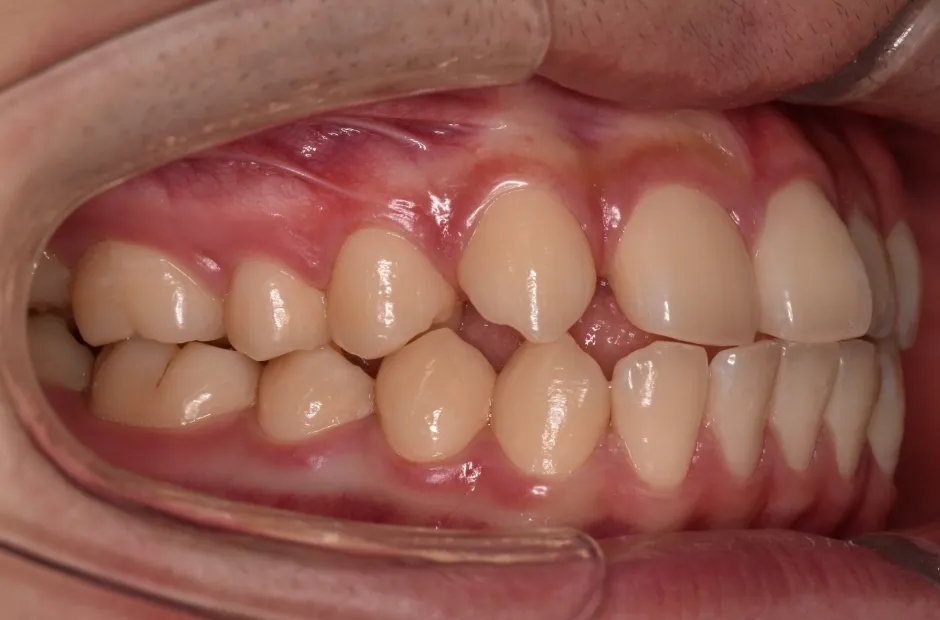

治療症例

ブラケット矯正

前歯部反対咬合

| 診断名・主訴 | 前歯部反対咬合 |

|---|---|

| 年齢・性別 | 14歳・男性 |

| 治療期間・回数 | 1年2か月 |

| 治療に用いた主な装置 | ブラケット矯正 |

| 抜歯部位 | なし |

| 治療費 | 60万円(税抜) |

| リスク・副作用 | 装置による違和感・疼痛・歯肉退縮・歯根吸収・虫歯のリスクなど |

治療前

治療後